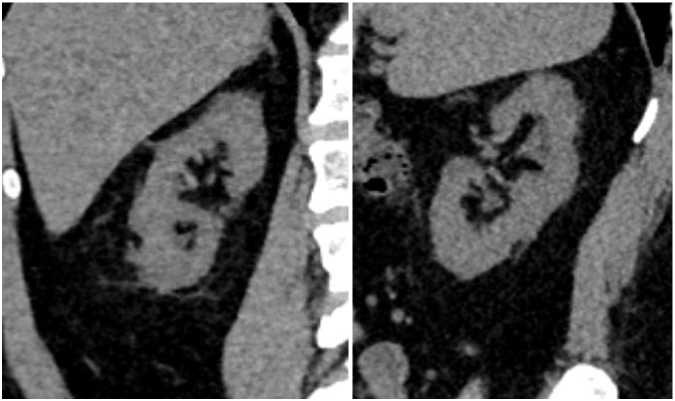

Рис. 3. МСКТ в нативном режиме, сделанная в июне 2023 г. Отмечен полный литолиз крупного камня ЛМС справа.

Рис. 4. МСКТ в нативном режиме, сделанная в июне 2023 г. Отмечено уменьшение камней нижней группы чашечек правой почки.

Рис. 5. МСКТ в нативном режиме, сделанная в июне 2023 г. Стрелкой указан конкремент нижней трети левого мочеточника, мигрировавший из области ЛМС.

слева, размерами до 4,8 x 3,5 мм, плотностью до +452 HU–при исследовании выявлен в нижней трети левого мочеточника. Левый мочеточник не расширен (Рис. 3–5).

Повторно обратилась за медицинской помощью, консультирована урологом НМХЦ им. Н.И. Пирогова, повторно предложено проведение оперативного вмешательства, от которого пациентка вновь решила воздержаться. Пациентке начата литолитическая терапия с целью возможного растворения камней ВМП путем коррекции кислотно-щелочного баланса мочи. Учитывая низкую ком-плаентность, крайне важно объяснить значимость непрерывного приема препаратов по чётко расписанной схеме лечения и постоянного динамического контроля показателей суточного анализа мочи с целью оценки pH мочи и степени урикемии. Литолитическая терапия проводилась с помощью цитрантых смеси. В течение последующего месяца пациентка стала отмечать постепенное купирование болевого синдрома, при контрольной КТ органов мочевыделительной системы, выполненной в августе 2023 г. (на 2-й месяц проводимой терапии) отмечено: ЧЛС обеих почек не расширена (ранее каликопиелоуретероэктазия справа). В нижней группе чашечек правой почки определяются два конкремента, размерами 2,3 x 1,8 мм и 2,4 x 2,6 мм, плотностью до +268 HU (ранее визуализировались не менее 3х конкрементов до 4 мм). В лоханке правой почки конкременты не выявлены (ранее конкремент размерами до 15 x 9,5 мм.) Мочеточник справа при нативном исследовании без значимого расширения, конкрементов в нем достоверно определяется. Выявляемые ранее уплотнение клетчатки на уровне лоханочно-мочеточникового перехода справа и увеличенный парааортальный лимфоузел справа–при настоящем исследовании не определяются. Конкременты левой почки не выявлены. Выявляемый ранее конкремент в области лоханочно-мочеточникового перехода